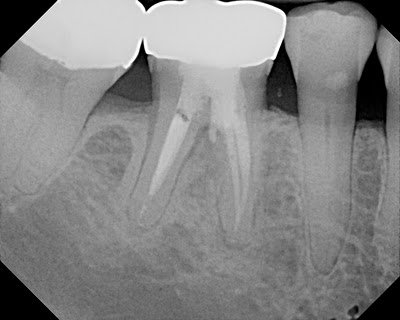

At 6 months, furcal and periapical lesion are improving and the tooth is functional.